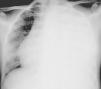

Presentamos el caso de una adolescente de 15 años de edad, sin antecedentes de interés, que presenta dolor dorsolumbar progresivo y astenia de 20 días de evolución. Dicho dolor genera disnea de pequeños-moderados esfuerzos. En la auscultación pulmonar se observa hipoventilación marcada en el hemitórax izquierdo. Se realiza radiografía de tórax (fig. 1) que evidencia derrame pleural masivo izquierdo, procediéndose a toracocentesis evacuadora sin dejar tubo de drenaje. Se evacúan 1.500ml de líquido pleural de coloración amarillenta (pH: 7,41 con predominio de linfocitos, glucosa: 82mg/dL, proteínas: 4,3g/dL, LDH: 391U/L y ADA: 26,3U/L). Evoluciona desfavorablemente, con aumento de la dificultad respiratoria y reacumulación de líquido en la cavidad pleural. Se realiza nueva toracocentesis, manteniéndose el drenaje con aspiración durante 5 días. Se obtienen aproximadamente 5 L de líquido con características de exudado. El despistaje microbiológico es negativo. En la resonancia magnética abdominal (fig. 2) se visualiza una masa retroperitoneal superior y lesiones focales que afectan a múltiples cuerpos vertebrales y a la cresta ilíaca izquierda, sugestivas de metástasis óseas.